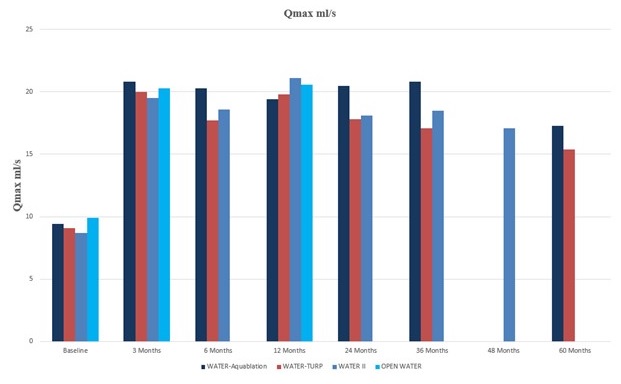

alternative resective procedures. In our U.S. pivotal trial, Waterjet Ablation Therapy for Endoscopic Resection of prostate tissue, or the WATER study, Aquablation therapy demonstrated superior safety and non-inferior efficacy results compared to transurethral resection of the prostate, or TURP, the historical standard of care for the surgical treatment of BPH. In the WATER and WATER II studies, surgical retreatment rates were only 5.2% at five years and 3.0% at four years, respectively. In the OPEN WATER study, there were no surgical retreatments at one year. The retreatment rates in the WATER and WATER II studies compare favorably to surgical retreatment rates observed for alternative treatments for BPH. One study published in the BJU International Journal reported on 52,748 men undergoing TURP or PVP with an approximated three-year freedom from surgical retreatment of 92% and 89%, respectively. A second study published in the Journal of Urology reported on 43,041 men undergoing TURP, PVP, enucleation, or open simple prostatectomy with an approximated three-year freedom from surgical retreatment of 93%, 89%, 94%, and 96%, respectively.

Clinical diagnosis of BPH typically involves a number of tests that are used to assess the degree of LUTS and determine whether the symptoms are caused by BPH or another condition. A symptom score index utilizes standardized questionnaires to quantify a patient’s degree of LUTS. One of the most common scoring systems is the International Prostate Symptom Score, or IPSS. Using this scoring system, LUTS are classified as either mild, moderate or severe. The IPSS questionnaire is a key tool used to evaluate treatment options and assess treatment success. Other commonly used tests include a digital rectal exam, urine sample tests, imaging scans, blood tests and uroflowmetry tests, which measure the strength and amount of urine flow during urination. Patients suffering from symptoms of BPH are typically first seen by a primary care physician, who may diagnose and manage the patient, or refer the patient to a urologist. A urologist is a physician who specializes in diseases of the urinary tract in both males and females as well as the male reproductive system. Urologists are trained to perform surgery for various types of urologic conditions, including BPH.

Drug Therapy

Drug therapy is often the first step in actively treating mild-to-moderate symptoms of BPH. While there is no pharmacological cure for BPH, drugs may be used to manage symptoms. Available drugs address symptoms by either shrinking (5-alpha reductase inhibitors) the prostate or relaxing (alpha blockers) muscles surrounding the prostate. In some instances, patients may be prescribed a combination of both medications. Most men with BPH who start drug therapy will need to continue it indefinitely in order to relieve symptoms, unless they choose to undergo surgical intervention. While drug therapy can provide relief for some men, two out of three patients are not satisfied with the effectiveness of their medication. In general, drug therapy provides IPSS reduction of approximately five points and flow improvement of up to 2.5 ml per second. Drug therapy is also often associated with negative side effects, including headaches, dizziness, nausea, erectile dysfunction, ejaculatory dysfunction, loss of libido, cardiac failure and dementia. These side effects often contribute to poor treatment compliance, with drug therapy failing in up to 30% of men within two years. Furthermore, drug therapy may be costly, particularly in light of limited symptom relief. For example, a recent study has shown that payor costs for branded combination drug therapy over a two-year period was the least cost-effective of all treatment options included in the study, as drug therapy requires extended use and yields the least symptom relief.

Resective Procedures. In resective surgery, tissue is removed during the procedure. Resective prostate procedures generally provide more significant and longer-lasting symptom relief than non-resective procedures, but may result in a higher incidence of irreversible complications, including urinary incontinence, erectile dysfunction and ejaculatory dysfunction. Resective procedures generally provide IPSS reduction of approximately 15 points. These procedures are typically performed in the hospital or outpatient surgery center under general or spinal anesthesia. In 2019, approximately 290,000 resective surgeries were performed in the United States, accounting for over 70% of all BPH surgeries.